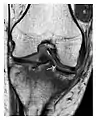

Fatigue fractures are more frequent in women which may be due to the relatively smaller bones of women. Moreover, pregnancy is a well-recognized risk factor for femoral neck fatigue fracture. While fibular and metatarsal fractures have a low risk of complications, other sites including the femoral neck, midanterior tibia, navicular, talar, and other intraarticular fractures are prone to complications such as delayed union, nonunion, and displacement. The site of the insufficiency fracture may be specific to the activity: for example, rugby and basketball players are more prone to navicular fractures, while gymnasts have a higher risk for talar fractures (Figure 7). Long distance runners are at increased risk for pelvic, tibial (Figures 8 and 9), and fibular fractures. In the military, calcaneus (Figure 10) and metatarsals are the most commonly cited injuries, especially in new recruits. Billiard players are at risk for upper limb fractures (Figure 11).[1]

Figure 9: Proximal metaphyseal fatigue fracture of the tibia in a 27-year-old recent male military recruit. (a) Anteroposterior radiograph is within normal limits. (b) Coronal T1-weighted MR image shows a marked linear hypoattenuation along the medial tibial metaphysis (arrow) surrounded by diffuse hypointensity in keeping with posttraumatic edema.[1]